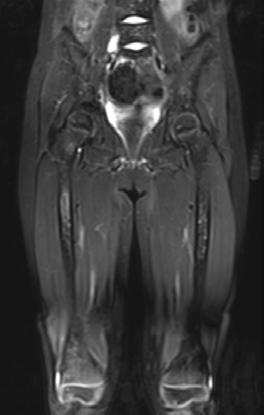

La historia clínica y la exploración física puede sugerir el diagnostico principalmente en miomas sintomáticos. La ecografía es el examen de elección para el diagnóstico de los fibromas uterinos.

La tomografía de abdomen puede ser útil en el diagnóstico pero más en la planeación para el tratamiento de los miomas uterinos ya sea quirúrgico, tratamiento de mínima invasión ó cuando se quiere descartar alguna patología asociada.

La Resonancia magnética no suele ser habitual por su alto costo y exposición a radiación para el diagnostico.

• Resonancia magnética de la próstata.